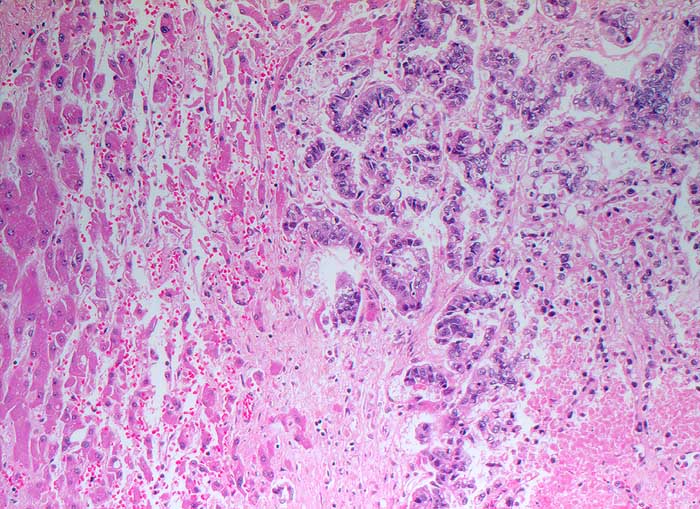

PathoPic ID 5606 - Wenig differenziertes Adenokarzinom: Lebermetastase

Wenig differenziertes Adenokarzinom: Lebermetastase

Links im Bild das durch die Metastase komprimierte Leberparenchym. Der partiell nekrotische Tumor rechts im Bild bildet drüsige Strukturen.

Lebermetastase bei unbekanntem Primärtumor